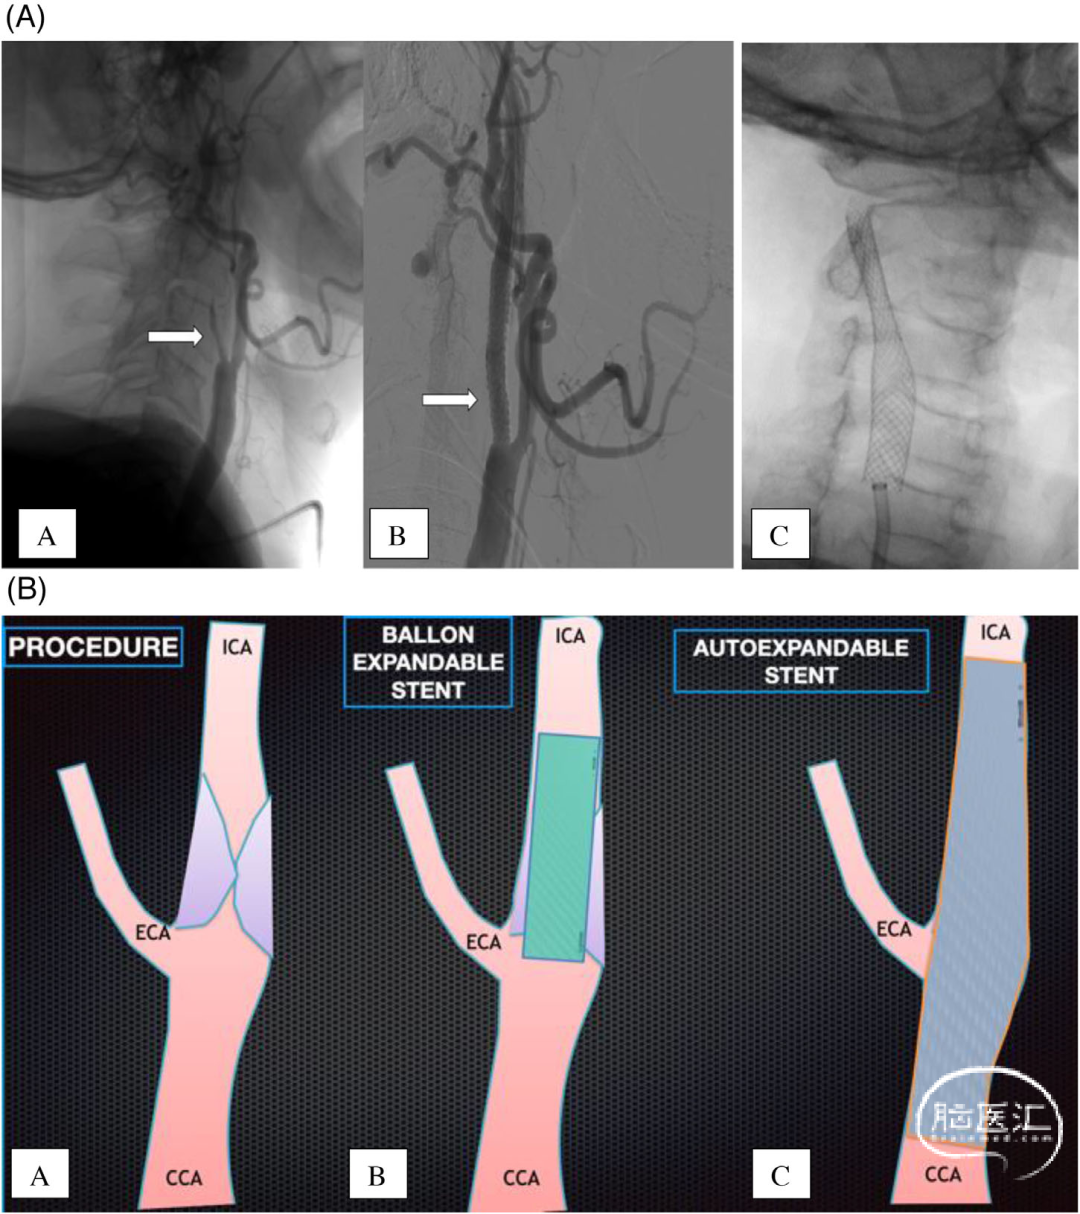

该研究回顾性分析2016年4月到2021年4月该中心由串联病变(ICA颅外段狭窄≥90%或闭塞)引起的前循环大血管闭塞AIS患者,所有患者均在急性期接受自膨颈动脉支架(SX)或球囊支架(BX)植入治疗。BX组患者急性期均选择最短的支架长度(仅覆盖ICA病变部分,不覆盖颈总动脉)。所有BX组患者在亚急性期(发病数天到数周)再次接受自膨支架植入术(要求覆盖颈内动脉病变以及颈总动脉)。SX组患者要求支架覆盖颈内动脉病变部分以及颈总动脉。具体见图1。SX组患者术前开始双联抗血小板治疗,持续至少术后90天。BX组患者术后开始采用单一抗血小板药物治疗,持续至少术后90天。

图1. 急性颈内动脉颅外段闭塞和球扩支架植入术。(A):A.右侧颈总动脉造影见颈内动脉起始部急性闭塞,B.球扩支架植入后造影可见颈内动脉血流恢复,C.另一个患者采用常规自膨支架植入。(B):A.急性颈内动脉串联狭窄病变引起急性闭塞,B.采用球扩支架植入术,只覆盖颈内动脉狭窄病变,C.再次采用自膨支架植入术,覆盖颈内动脉狭窄病变以及颈总动脉。